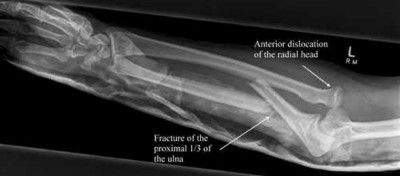

A 12-year-old male sustains an ulnar fracture with an associated posterior-lateral radial head dislocation. After undergoing closed reduction, the radiocapitellar joint is noted to remain non-concentric. What is the most likely finding?

In pediatric Monteggia fractures the annular ligament is commonly interposed in the radiocapitellar joint.

Bado initially described and classified Monteggia fractures. The most common injury pattern is an extension type 1 with anterior radial head dislocation and apex anterior ulnar shaft fracture. The apex of the ulna fracture determines the direction of the radial head subluxation or dislocation. Adults typically require ORIF of the ulna. These fractures in children are often treated non-operatively with closed reduction if the ulna fracture is transverse and stable. Type III is the one most commonly associated with irreducibility of the radial head because of interposition of the annular ligament. The incidence of posterior interosseous nerve injury is high with this lesion. The nerve deficit usually completely resolves rapidly and spontaneously.

Tan et al reviewed their treatment of 35 children with Type I and Type III Monteggia fractures. All radial heads were explored and the interposed annular ligament was stretched out of the joint space. They noted that none of the patients had any recurrent dislocation or subluxation.

Ring et al in their review stress the importance of an anatomic reduction of the ulna to restore the reduction of the radial head.